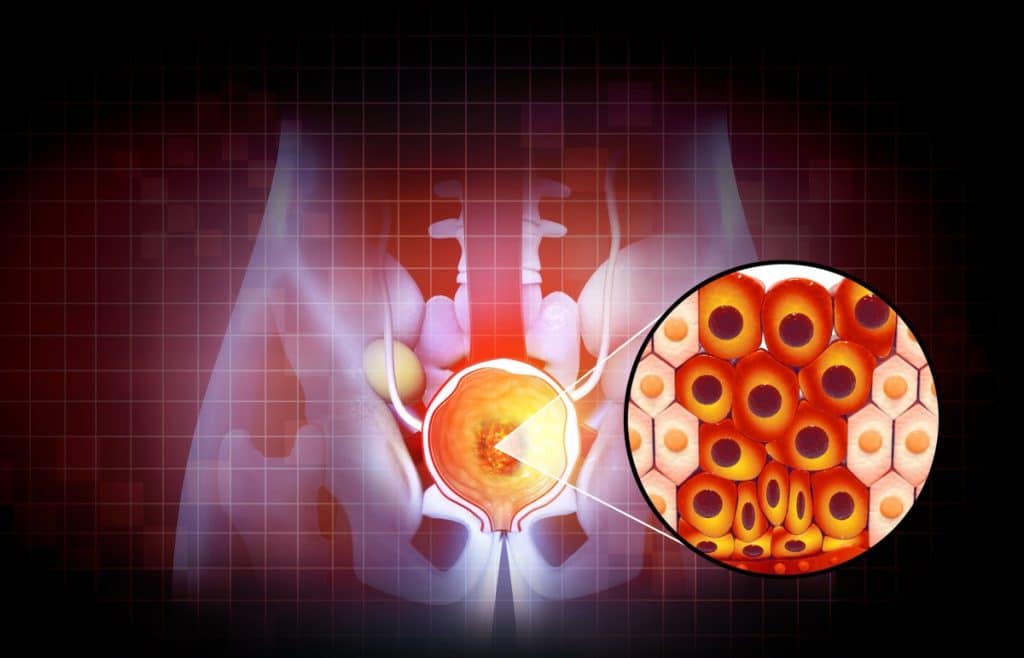

Prostata jer organ žlijezda kod muškaraca smještena ispod mokraćnog mjehura, a osnovna funkcija je proizvodnja sekreta u zdravom sjemenu te štiti sjeme u sjemenoj tekućini na putu do jajne stanice. Također ima ulogu i kod kontrole mokrenja jer kroz prostatu prolazi mokraćna cijev. U starijoj dobi dolazi do uvećanja prostate pa time i do otežanog mokrenja.

Kada se dijagnostikom otkriju tvorbe na prostati potrebno je ispitati stanice te tvorbe kako bi se ustanovilo radi li se o zloćudnim stanicama. Postupak uzimanja tkiva je biopsija prostate za phd analizu kojom će se utvrditi o kakvoj se tvorbi radi.

Biopsija prostate se radi uz lokalnu anesteziju koja se napravi uz pomoć gela lidokaina kojeg se stavlja na kraj debelog crijeva. Uzorak koji je pribavljen iglom daje se na analizu patologu koji će uz pomoći specijalnih metoda probira kroz mikroskop promatrati stanice uzetog tkiva. Ukoliko u uzorku postoje patološke stanice zloćudnog tkiva patolog će ustanoviti stupanj agresivnosti kancerogenih stanica. Ovo je vrlo važno za potrebe liječenja da se odredi vrsta karcinoma te da se primjeni pravilna doza lijekova i način liječenja.

Biopsija prostate je preventivna mjera kao što je i specijalistički pregled prostate. Uzimanjem tkiva prostate za koje se sumnja da ima patološke promjene, te njihovim analiziranjem može se točno utvrditi radi li se o kancerogenom tkivu i vrsta kancerogenog tkiva. Određivanjem vrste kancerogenog tkiva se ustanovljuje koliko brzo se otkriveni karcinom širi na okolno područje prvenstveno mokraćni mjehur.